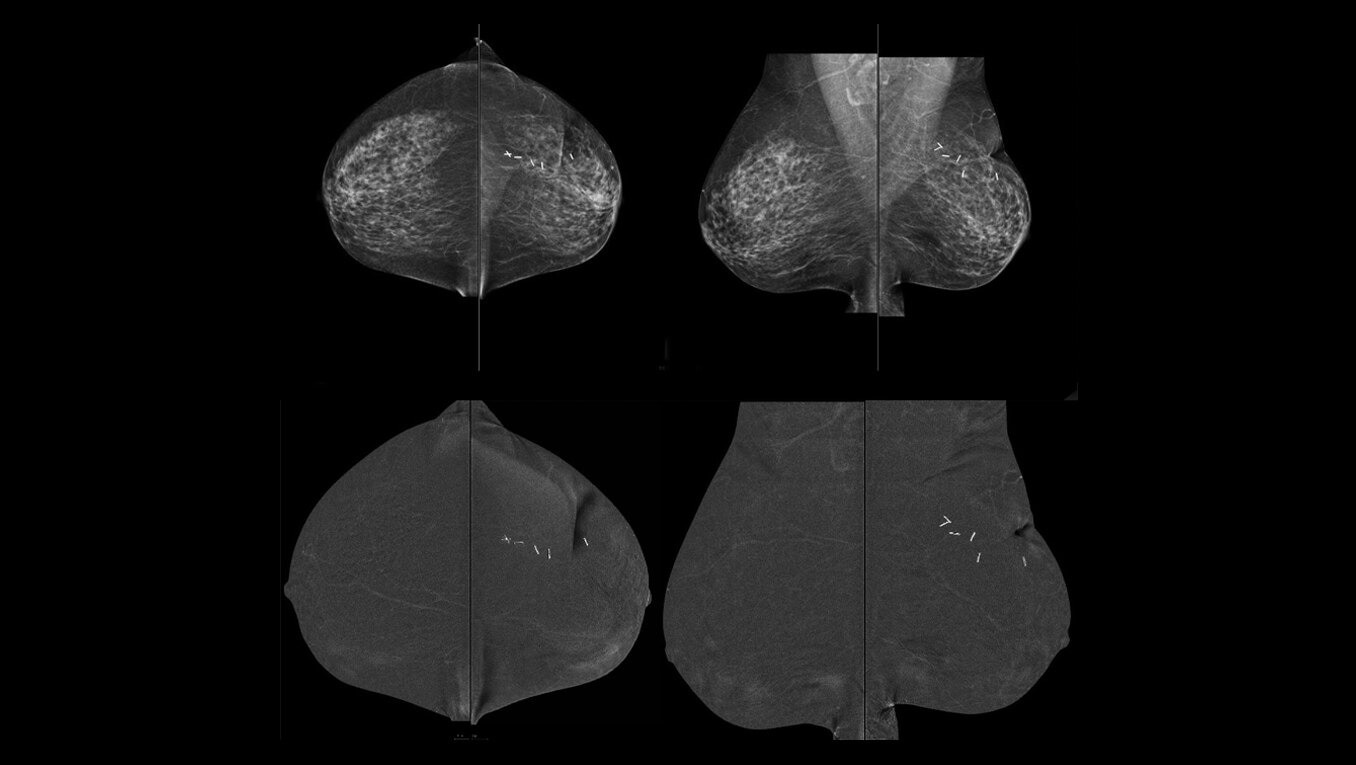

GE HealthCare pioneered this technology in 2010 and is associated with over 200 publications that demonstrate its clinical performance. GE HealthCare’s CEM combines the morphologic and density information similar to a conventional mammogram and the functional vascular information of a breast MRI1. It presents an opportunity to create and implement a more streamlined workflow to help diagnosis breast cancer early. In addition to increasing patient access, our CEM offering boasts high levels of sensitivity and specificity, allowing for the detection of lesions that would otherwise go undetected2,3,4. To ensure your practice can fully leverage the combined power of GE HealthCare contrast mammography solutions, we introduce Pristina Bright our comprehensive CEM package with complete support, from training to service, for your successful implementation.